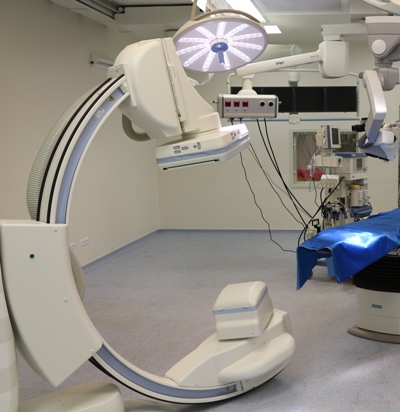

Este un caz fericit pentru pacientul din Italia şi de succes pentru secţia Neurochirurgie, dar şi pentru întreaga instituţie medicală, or, astfel de intervenţii complicate au devenit posibile în Republica Moldova în urma deschiderii noului Bloc chirurgical în luna mai curent, prin intermediul căruia ţara noastră a obţinut facilităţi şi posibilităţi care au existat pînă nu demult doar în centrele medicale contemporane performante din lume. Astfel, sala de operaţii Hybrid a blocului dispune de metode de neuroimagistică intraoperatorie şi sisteme de monitoring şi neuronavigaţie, sisteme specializate de implanturi din titan şi instrumente chirurgicale, echipamente pentru disecţie osoasă. Acest complex chirurgical este completat de un departament ultradotat de anestezie şi neuroreanimare, care asigură o parcurgere perioperatorie fără complicaţii.